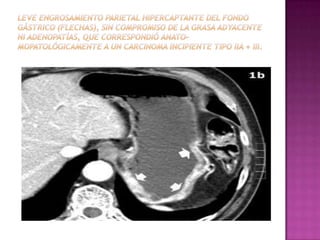

 Un tumor 1RIO tipo II b /CA gatrico

precoz, no se detecta MPR ni gastroscopia

virtual, solo Con CX.